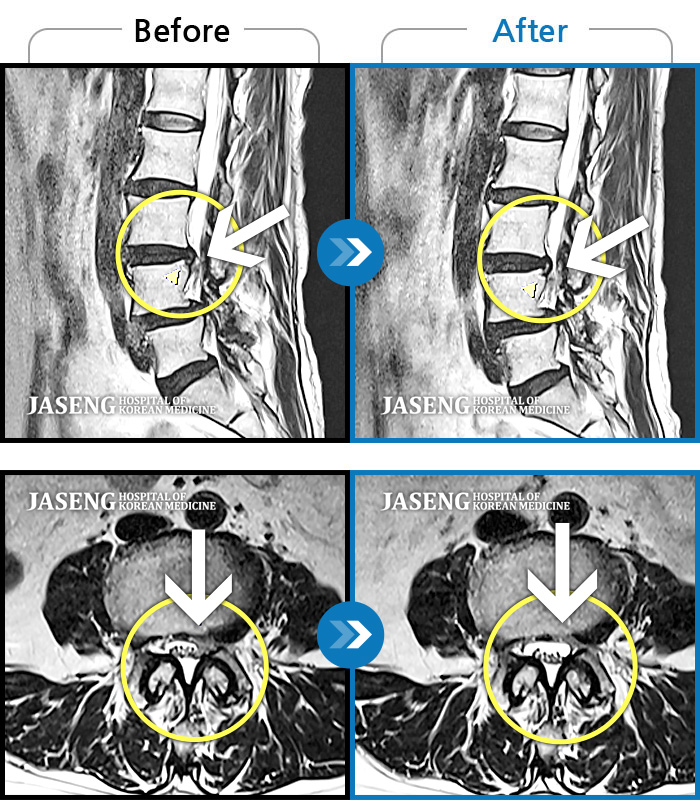

허리디스크

광주 · 김동은 원장

좌측 골반 및 종아리부터 발까지 이어지는 저림과 통증으로 내원하셨습니다.

촬영시기

2023.10.03 ~ 2025.08.14

2025.08.22